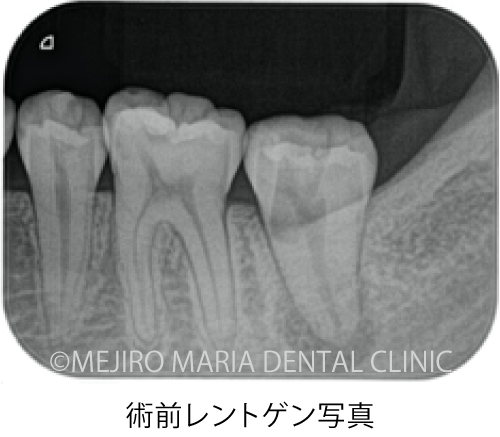

当院での初診時の検査でレントゲンを確認すると、歯冠(歯肉の上に出ている歯の部分)に人工的な透過像が確認でき、前医での治療の際に、偶発的に歯に穴(穿孔・パーフォレーション)が開けられてしまったことが予想できました。また、歯肉(歯ぐき)が大きく腫れあがり、限局的な歯周ポケットが確認される上に、穴のあいている部分と歯周ポケットが交通している可能性も考えられるなど、状況は複雑化していました。

顕微鏡下で根管内を確認すると、レントゲン透過像通りに穴があいていること(穿孔)が確認され、実際の根管は治療が手つかずのままでした。